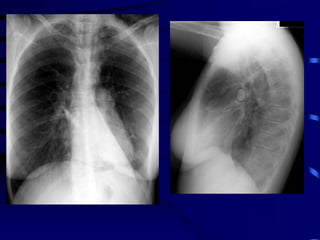

obstruction

 Small airways

Air Trapping

 Hyperinflated chest

 Barrel shaped

 Loss of cardiac dullness

 Liver pushed down